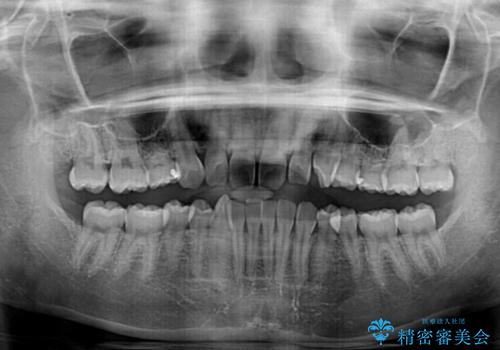

上顎に乳歯が左右1本ずつ残っていたため、若干咬み合わせに不具合が残りましたが、強い咬合力の原因であったディープバイトをしっかりと改善することができました。

- 前歯のデコボコと強い咬みしめを気にして来院された患者様です。

インビザラインを用いて、前歯の叢生を解消するとともに、ディープバイトを改善していくこととしました。